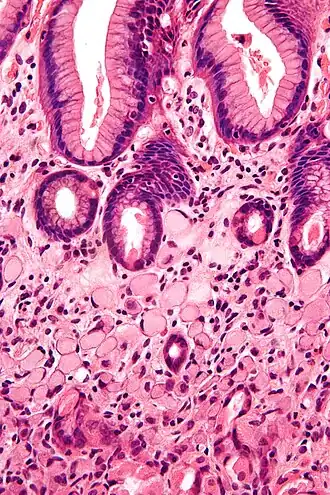

Histologia

O carcinoma de células escamosas surge da multiplicação descontrolada de células do epitélio e podem conter queratina e redes de filamentos ou desmossomos. Existem 6 sub-tipos: Adenoide, basaloide, células claras, células espinosas, células em anel de sinete e pleomórfico.